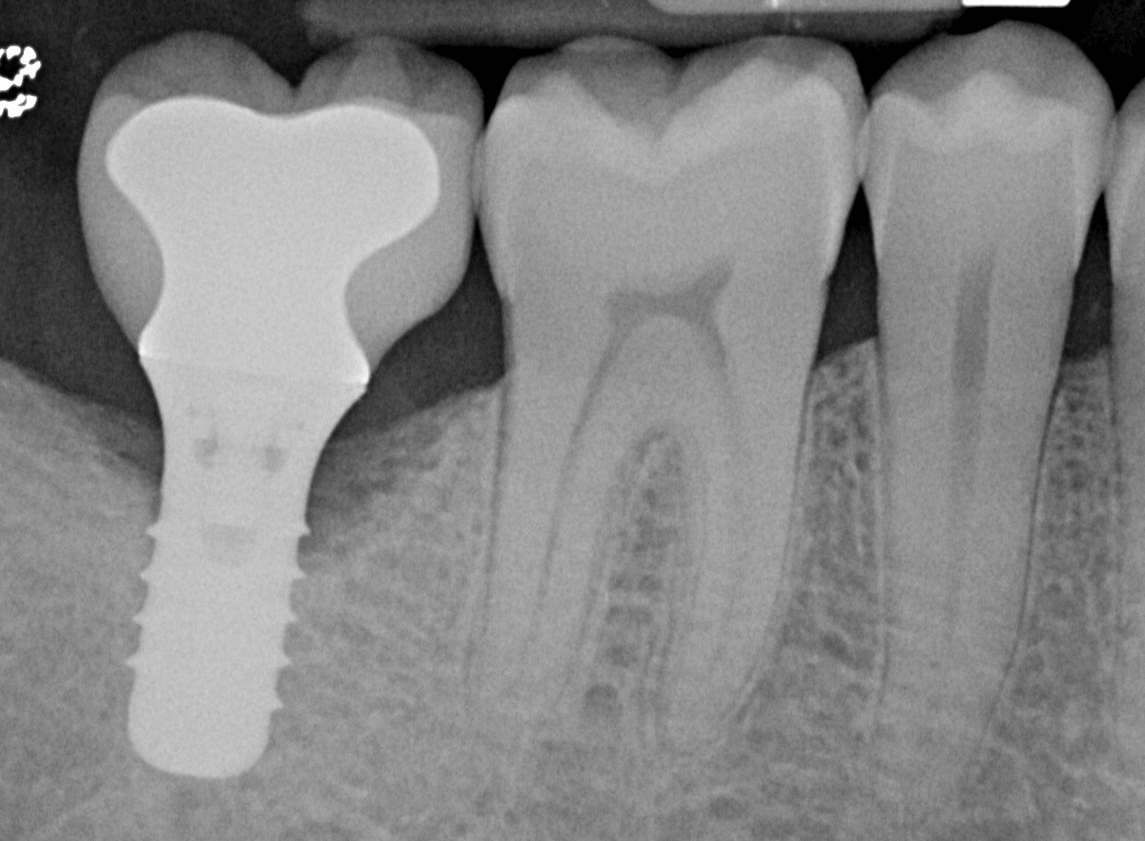

Pretreatment radiograph of a peri-implantitis

lesion on a 51-year-old male patient with a noncontributory medical history. The implant had been placed 3 years prior and presented with 8 mm pocketing with purulence.

Figure 1

At 1 year following treatment, probing depths are now 3 mm with an absence of bleeding.

Figure 6

Figure 7